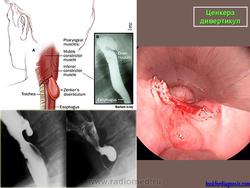

ГЛОТОЧНО-ПИЩЕВОДНЫЕ ДИВЕРТИКУЛЫ

Данная разновидность мешковидных выпячиваний стенки пищевода впервые описана F. A. Zenker и носит его имя, однако о ней упоминал еще К. Людлов в 1764 г.

Глоточно-пищеводные (гипофарингеальные, ценкеровские) дивертикулы составляют от 1,3 до 5 % от всех дивертикулов пищевода, т. е. являются довольно редким заболеванием [Ванцян Э. Н., 1963; Розенфельд Л. Г., 1965; Тамулевичуте Д. И., Витенас А. М., 1986]. Мужчины страдают им в 3 раза чаще, чем женщины, что, по всей видимости, связано с несколько большими размерами гортани у лиц мужского пола. Обнаружение ценкеровских дивертикулов у пациентов моложе 15 лет относится к области казуистики.

Местом расположения глоточно-пищеводных дивертикулов является так называемый треугольник Ланье — Хаккермана, боковые стороны которого образованы волокнами щитоглоточной части нижнего констриктора глотки, а основание — перстнегло-точной частью той же мышцы. Упомянутое анатомическое образование есть своего рода место наименьшего сопротивления, где нижний отдел глотки сдавливается между позвоночником и гортанью.

Ценкера дивертикул.

Дивертикул Ценкера.